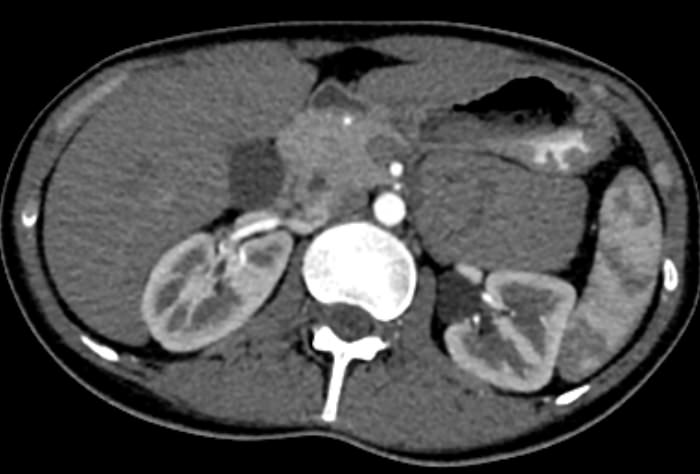

Мультиспиральная КТ сосудов почек (КТ-ангиография) с внутривенным болюсным контрастированием проводится для диагностики патологии почечных артерий. С помощью КТ-ангиографии можно выявить врожденные аномалии развития сосудов почек, диагностировать стенозы (уменьшение просвета) почечных артерий за счет развития атеросклеротических бляшек.

КТ сосудов почек применяется для выявления признаков вторичной артериальной гипертензии, при планировании оперативных вмешательств и для оценки успешности проведенной операции на сосудах. КТ ангиография почечных артерий позволяет оценить их анатомию, выявить добавочные и аберрантные почечные сосуды, определить типично ли они распространяются в ворота почки или заходят в паренхиму через корковый слой.

Чувствительные детекторы улавливают рентгеновские лучи после их прохождения сквозь тело человека. На основании этих данных получаются изображения сосудистой системы почек в мельчайших подробностях. Кроме того, с помощью цифровой обработки данных томограф реконструирует трехмерные модели кровеносных сосудов на уровне исследуемой области. 3D-реконструкции помогают увидеть пространственное соотношение анатомических структур и значительно повышают качество диагностики.

В наших медицинских центрах КТ-ангиография почечных артерий выполняется на новейших мультиспиральных компьютерных томографах экспертного класса TOSHIBA AQUILION. Аппараты сканируют область почек, производя одномоментно множество послойных срезов исследуемой зоны, благодаря этому создаются изображения кровеносной системы высокого качества. Это позволяет проводить точную и достоверную диагностику патологии почечных артерий. При этом за счет скоростного мультисрезового сканирования пациент получает минимальную дозу рентгеновского облучения.